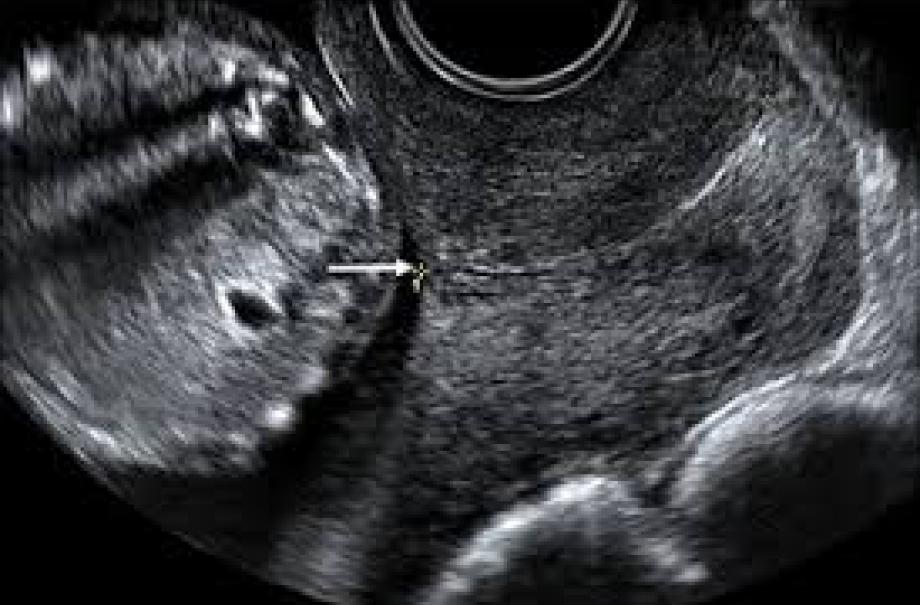

This is a transvaginal scan to measure the length of the cervix.

• Transvaginal Scan

• Measurement of the  Cervix.